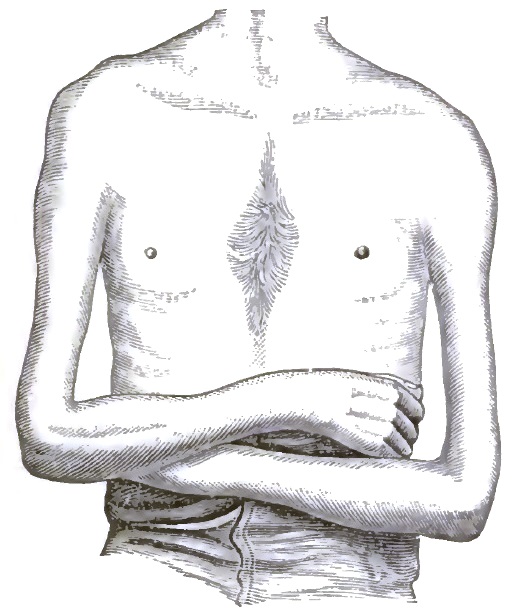

Professor of Pathology and Practical Medicine in the College of Physicians and Surgeons, New York.

DUDLEY, EDWARD C., A.B., M.D.,

| 33. | SHOWING ATROPHY OF THE RIGHT DELTOID AND ARM, AND OF THE LEFT ARM |

| 34. | SHOWING ATROPHY OF THE DELTOID, POSTERIOR ASPECT, AND OF THE SCAPULAR MUSCLES |